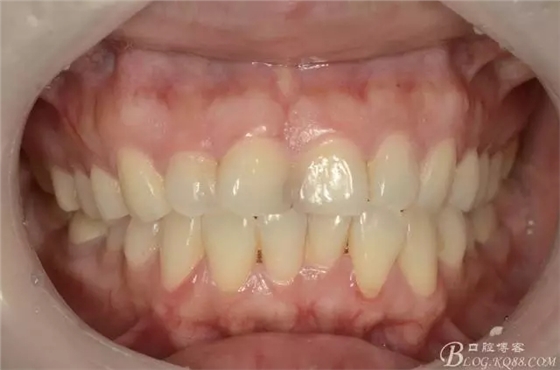

患者,女,33歲,酒吧歌手

主訴:門牙變黑一年余,要求診治

現(xiàn)病史:患者訴一年多以來,自覺門牙越來越暗黑,影響美觀與交際,不敢大笑,遂前來就診

口腔檢查:11與21之間可見齲壞,探診未見明顯疼痛與缺損,牙齦未見明顯紅腫,無叩痛,冷熱刺激無不適,未見松動(dòng)。兩近中切角收少許,舌側(cè)中1/3課件齲壞,探診可有粗糙感,質(zhì)地硬而黑,牙線經(jīng)過鄰面未見異常,切端可見少許磨耗,咬合張口可,關(guān)節(jié)無壓痛彈響,淺覆合淺覆蓋。

1)術(shù)前照